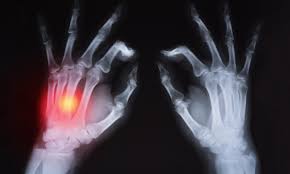

1. 손과 손목

일반적으로 손가락, 손목의 작은 관절에서 시작됨.

- 류마티스 결절 : 관절 근처 피부 아래의 단단한 덩어리

- 관절 삼출액 : 관절 내부에 비정상적인 체액 축적

- 관절 강성 : 움직이기 어렵거나 운동 범위 손상

- 척골 드리프트 / 척골 이탈 : 손가락이 새끼손가락 쪽으로 기울어지는 것처럼 보이는 특징적인 기형

- 구축 : 근육과 결합 조직이 짧아 지거나 굳어 져 기형과 단단한 관절이 생깁니다.

- 손목 아 탈구 : 부분 탈구

7. 관절 아 탈구 및 탈구

X- 레이에서 볼 수있는 관절 침식은 관절 이동성 및 기능의 제한과 관련이 있습니다. 도 9는 공동이 침식되고 연골이 손상되기 때문에, 뼈의 뼈 접촉은 통증 최종 결과 일 수 있다.

연골, 힘줄, 인대 및 뼈의 심각한 손상은 관절을 불안정하게 만들 수 있습니다. 관절 불안정성은 아 탈구 또는 덜 자주 탈구로 이어질 수 있습니다 .

많은 관절이 RA로 인해 변형되거나 아 탈구 될 수 있지만 발가락이 더 일반적인 관절 중 하나입니다. 연관된 통증, 손상 및 기능 제한은 종종 이동성의 손실로 이어집니다.